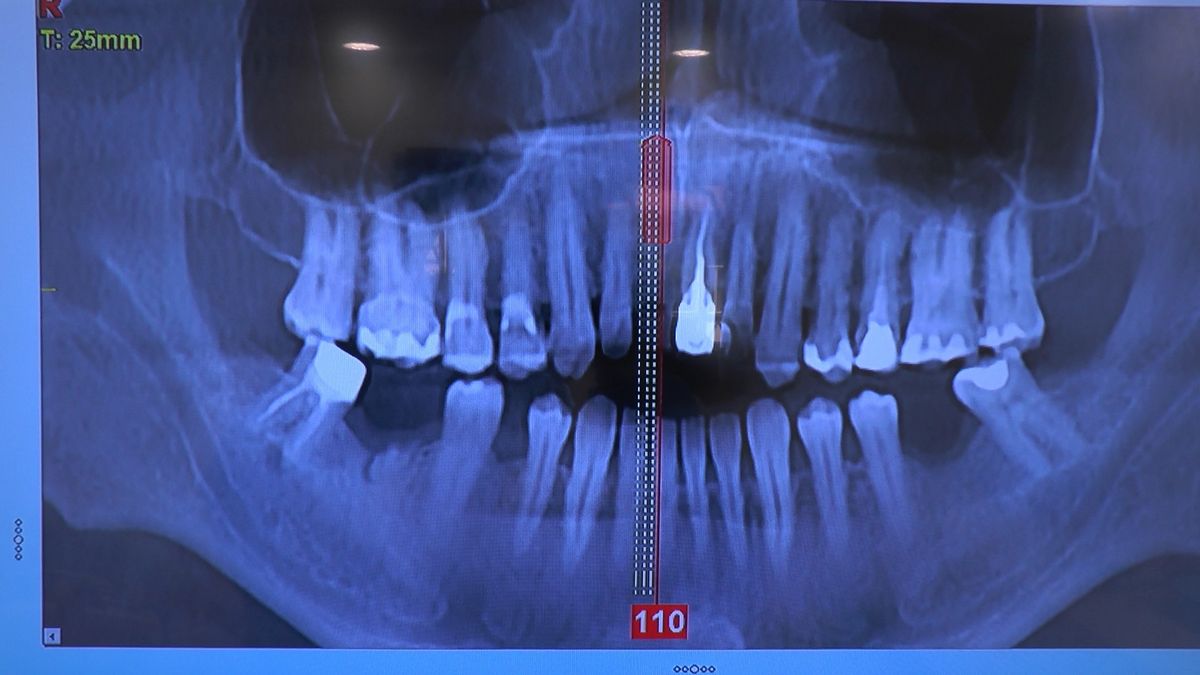

W ostatni weekend czerwca 2018 roku kursanci II Sezonu Preludium Implantologii odbyli piątą, finałową sesję, która w całości podporządkowana była praktyce. W ciągu dwóch dni zabiegowych Lekarze uczestniczący w szkoleniu przeprowadzili szereg zabiegów pod kierunkiem dr n.med. Violetty Szycik. Wszczepili 17 implantów oraz przeprowadzili ekstrakcje i zabiegi regeneracyjne kości. Zabiegi były wykonywane także w sedacji dożylnej z udziałem specjalisty anestezjologii i intensywnej terapii dr Jolanty Grzybowskiej. Preludium implantologii to nowy program edukacyjny dla adeptów implantologii stomatologicznej, którego celem jest wprowadzenie do implantologii poprzez pozyskanie wiedzy w szerokim zakresie i uwzględnieniem szczegółów mających decydujące znaczenie dla powodzenia leczenia implantologicznego. Ale tak jak wszystkie szkolenia w Instytucie Vivadental, w tym wiodące Practiculum Implantologii, zorientowane jest na praktyce i samodzielnym wykonywaniu zabiegów pod kierunkiem Mentora. To najlepsza edukacja w medycynie zabiegowej, a zarazem najlepszy start do implantologii.